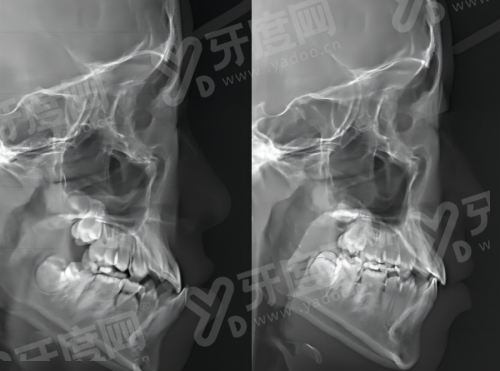

1、上海臻吻口腔医院引进数字化口腔CT设备,能清晰呈现牙槽骨密度、牙齿根部结构等细节,为种植牙、牙齿矫正等项目提供精细的影像支持,辅助医生制定个性化诊疗方案。